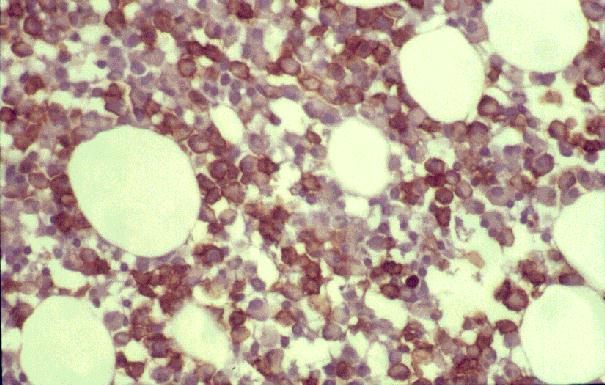

Los síndromes hipereosinofílicos (SHE) constituyen un grupo raro y heterogéneo de trastornos, definidos como eosinofilia persistente y marcada en sangre (> 1,5 × 109/L durante más de seis meses consecutivos) asociada con evidencia de daño orgánico inducido por eosinófilos, habiendo excluido otras causas de hipereosinofilia como trastornos alérgicos, parasitarios y malignos.

Los SHE se manifiestan con mayor frecuencia en pacientes jóvenes o de mediana edad, pero pueden afectar a cualquier grupo de edad. Se ha descrito una predominancia en hombres (relación 4 a 9:1) en series históricas, pero es probable que esto refleje la casi exclusiva distribución masculina de la mutación de una célula madre hematopoyética esporádica encontrada en una variante de la enfermedad recientemente caracterizada. Los daños en órganos diana mediados por eosinófilos son altamente variables entre pacientes, con afectación de la piel, el corazón, los pulmones y los sistemas nerviosos central y periférico en más del 50% de los casos. Otras complicaciones frecuentemente observadas incluyen hepatomegalia y/o esplenomegalia, gastroenteritis eosinofílica y trastornos de coagulación.

Recientemente se ha establecido que la hipereosinofilia puede deberse a una afectación primitiva de las células mieloides, esencialmente causada por una deleción cromosómica intersticial en 4q12 que conduce a la creación del gen de fusión FIP1L1-PDGFRA (variante F/P+), o al incremento de la producción de interleucina (IL)-5 mediante una población de células T expandidas de forma clonal (variante linfocítica), más frecuentemente caracterizada por un fenotipo CD3-CD4+.